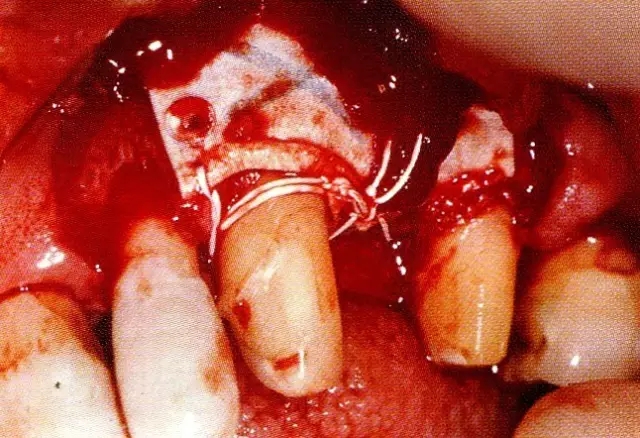

640.webp (2).jpg

▲圖7-3  將posterior interproximal類型的非吸收性覆膜修整后進行垂直懸吊縫合做固定。垂直懸吊縫合后,確定覆膜是否會動搖,再將齦瓣與之緊密縫合。